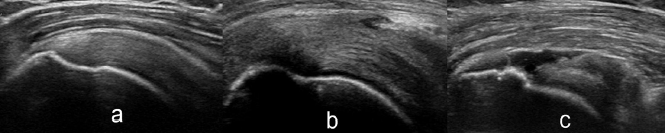

Cuff integrity was evaluated by ultrasound.Below are the ultrasound images of an intact cuff (a), partial tear (b), and full thickness tear (c).

Full thickness tears (FTRCT) were found in 23 subjects (4.7%) but only in those aged ≥49 years. Subjects aged 50-59, 60-69, and ≥70 years of age had FTRCT prevalence rates of 3.5%, 13.3%, and 11.1%, respectively. The prevalence of FTRCTs was higher in subjects with diabetes (P = .042) and a smoking history (P= .002), but no differences were noted for the presence of thyroid disease (P = .051).

Comment: In this series of 486 volunteers without any shoulder complaints, the comfort and function were not affected by the integrity of the cuff. This again points to the observation that full and partial thickness cuff tears can be asymptomatic.